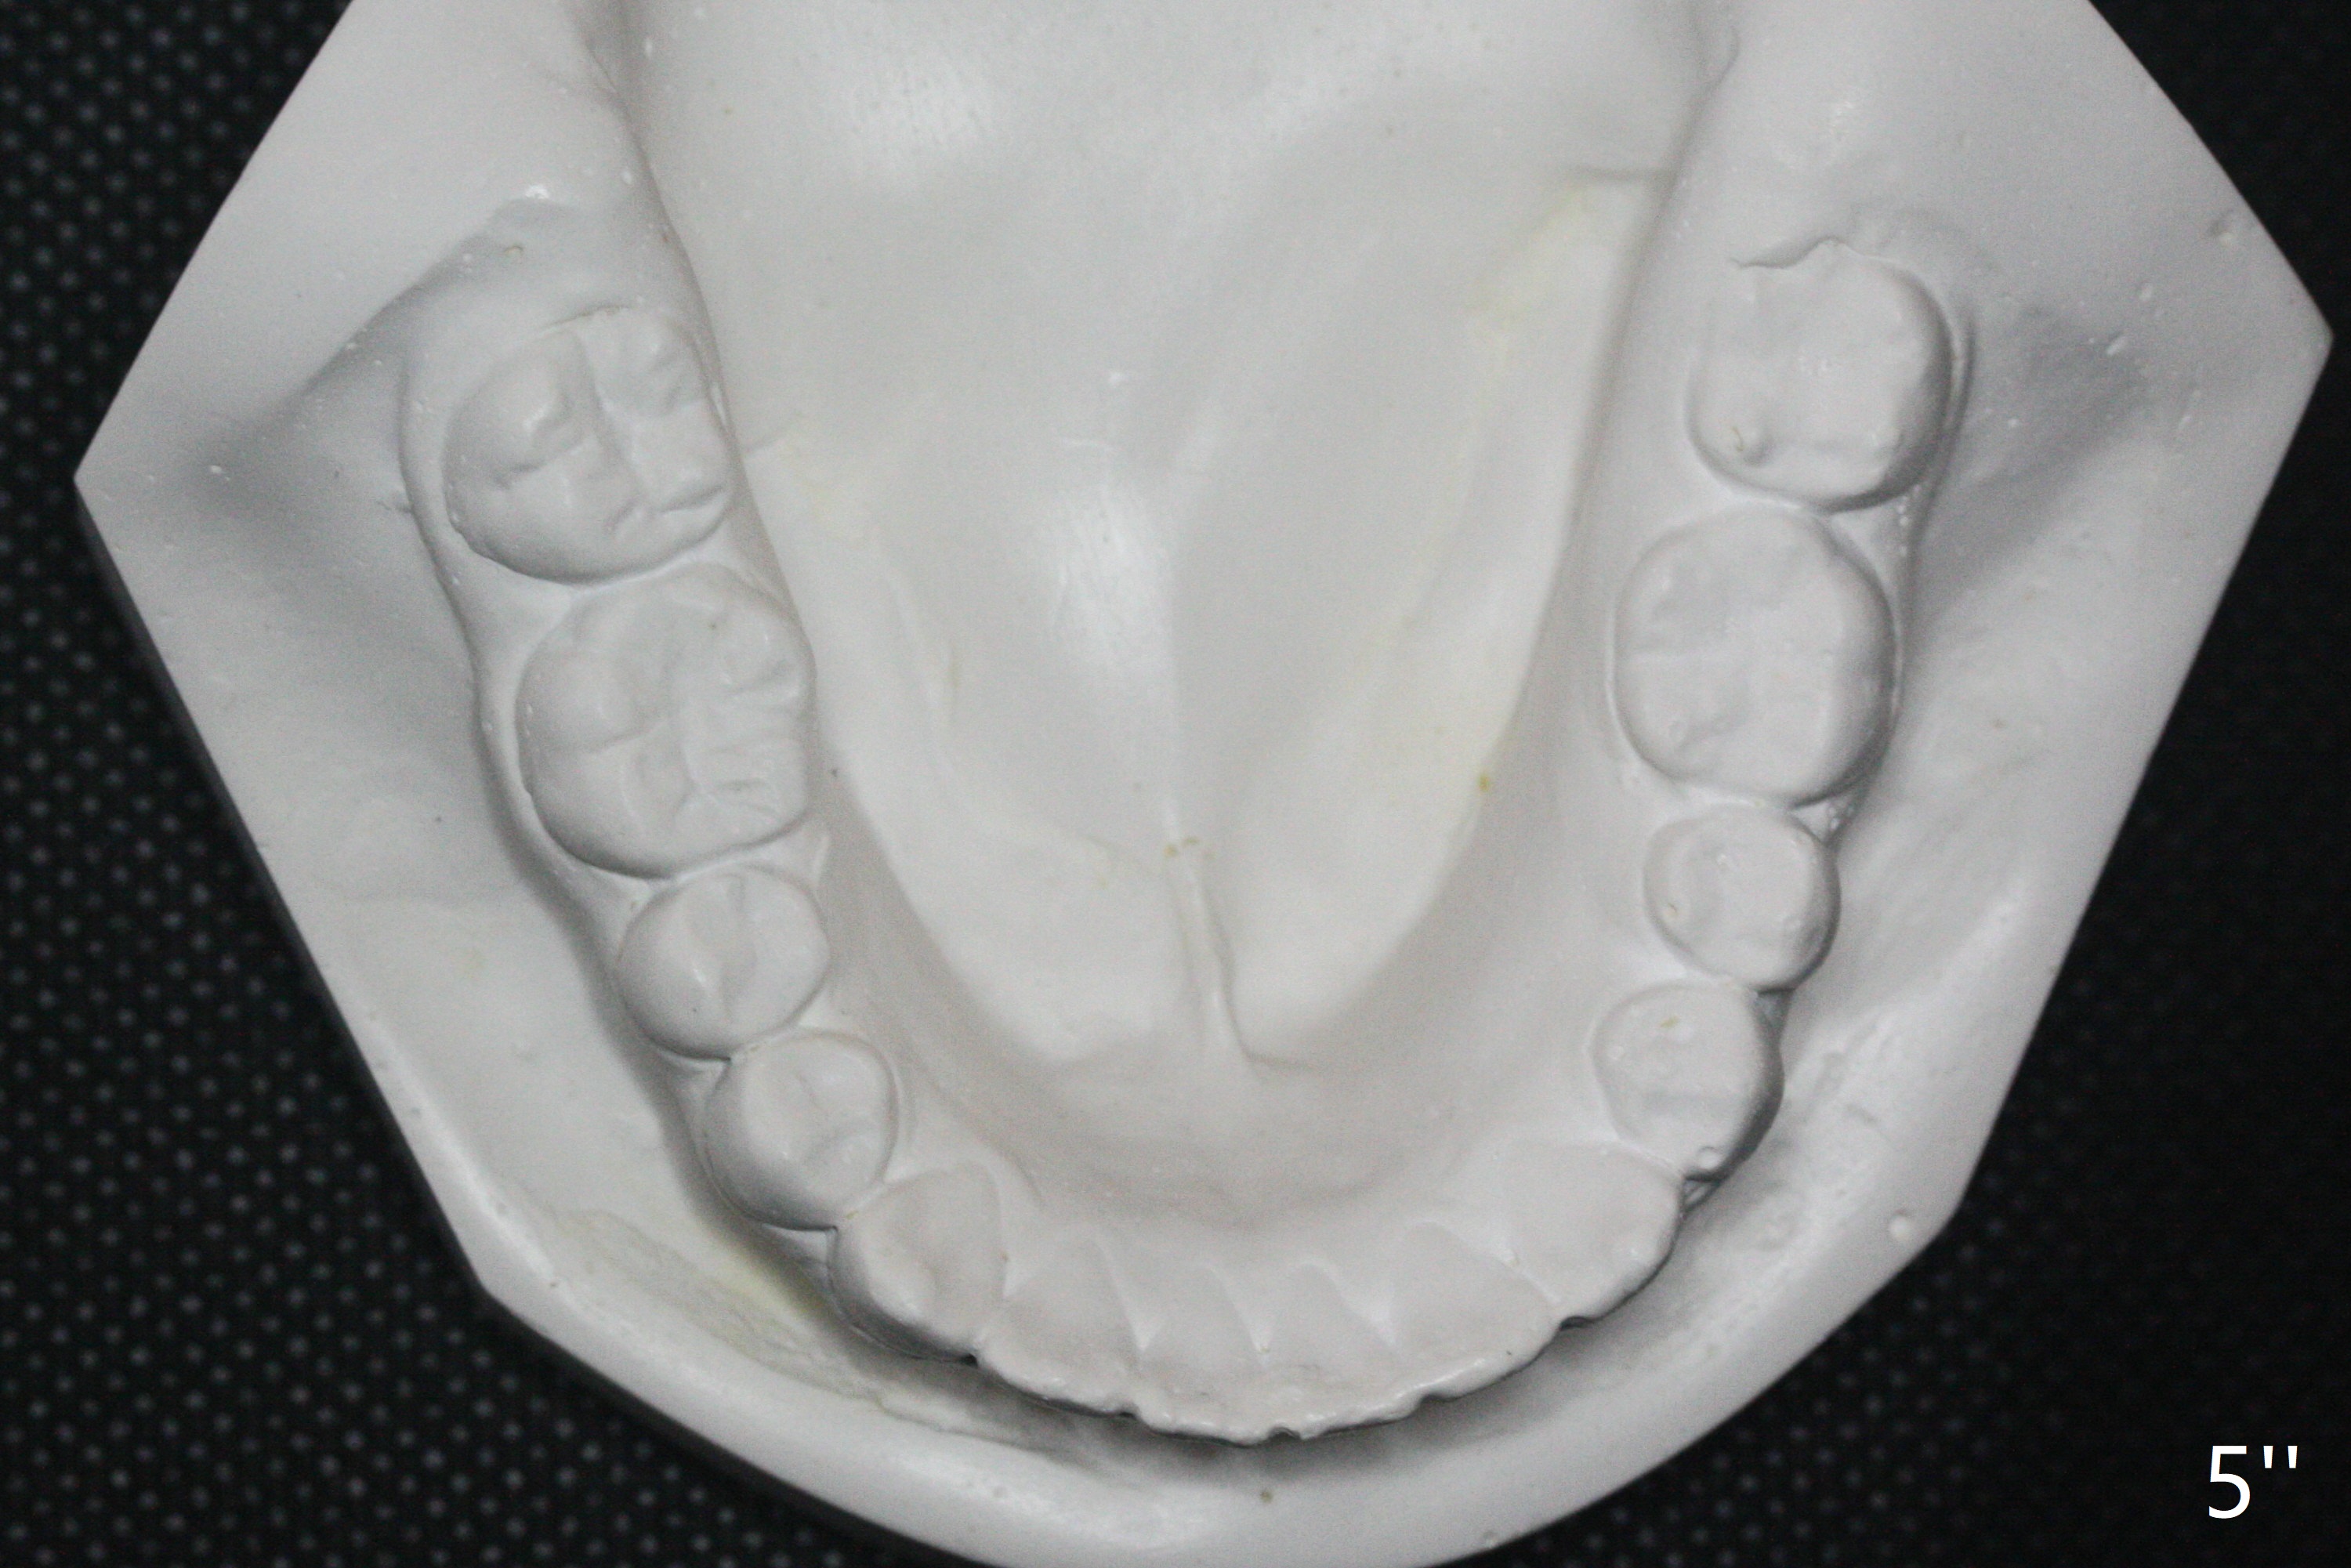

A 12-year-old woman has severe crowding including UL7 impaction (Fig.1-5), finishes non-extraction orthodontics at the age of 15 (Fig.1'-5') and returns for retainer remake at 19 (Fig.1''-5''). Four years post debanding, UL7 (Fig.4') seems to improve its position (Fig.4'').